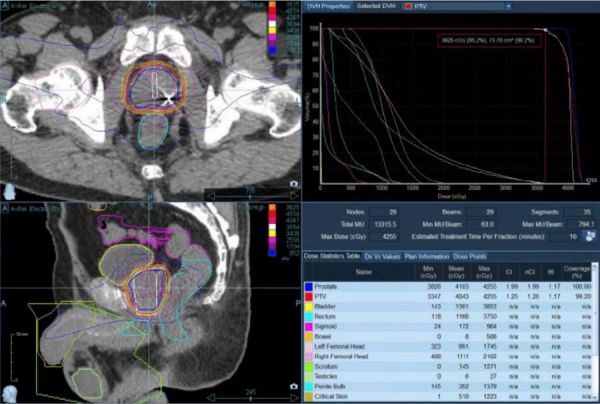

Capital Radiosurgery Centers (CRC) provides highly precise, non-invasive prostate cancer treatment using advanced radiation technologies such as stereotactic radiosurgery (SRS), stereotactic body radiation therapy (SBRT), and intensity-modulated radiation therapy (IMRT). Treatment plans are developed based on clinical appropriateness and delivered by a team of board-certified radiation oncologists and highly trained oncology specialists.

These treatments deliver targeted radiation directly to the prostate with sub-millimeter precision, helping preserve surrounding organs such as the bladder and rectum while maintaining quality of life. Care is provided in an outpatient environment, allowing patients to receive highly effective treatment without surgery, anesthesia, or extended recovery time.

SBRT is an advanced radiation therapy that targets tumors with sub-millimeter accuracy. Unlike conventional radiation, which may take weeks, SBRT completes treatment in days—protecting healthy tissue and helping patients maintain their daily routines.

We use CyberKnife® and Varian TrueBeam® to treat tumors anywhere in the body, even those that move with breathing or normal motion. Advanced imaging and real-time tracking mean no restrictive frames, no breath-holding, and no invasive procedures.